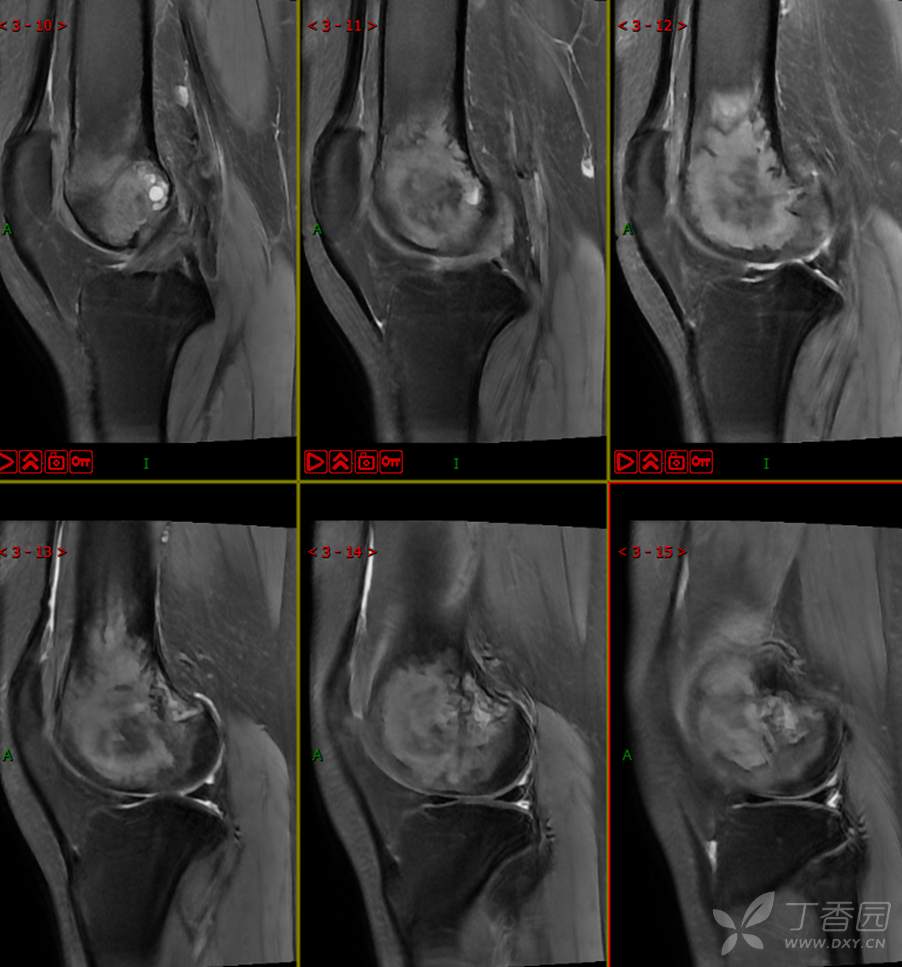

【影诊笔记497】左膝关节疼痛不适1周余就诊,有点难度~『骨巨细胞瘤』

主 诉:左膝关节疼痛不适1周余。

现病史:患者1周余前无明显原因及诱因出现左膝关节疼痛不适,活动时疼痛加重,休息后好转,无明显关节不稳及交锁,无发热、盗汗、乏力,无胸闷、憋气,无头痛、头晕,无四肢小关节晨僵。曾于外院就诊行左膝DR检查示:左股骨远端肿物。现患者为进一步治疗于我院就诊,门诊经检查后以“左股骨远端肿物”收入我科。患者自起病以来,神志清,精神可,饮食睡眠可,大小便正常,体重无明显减轻。